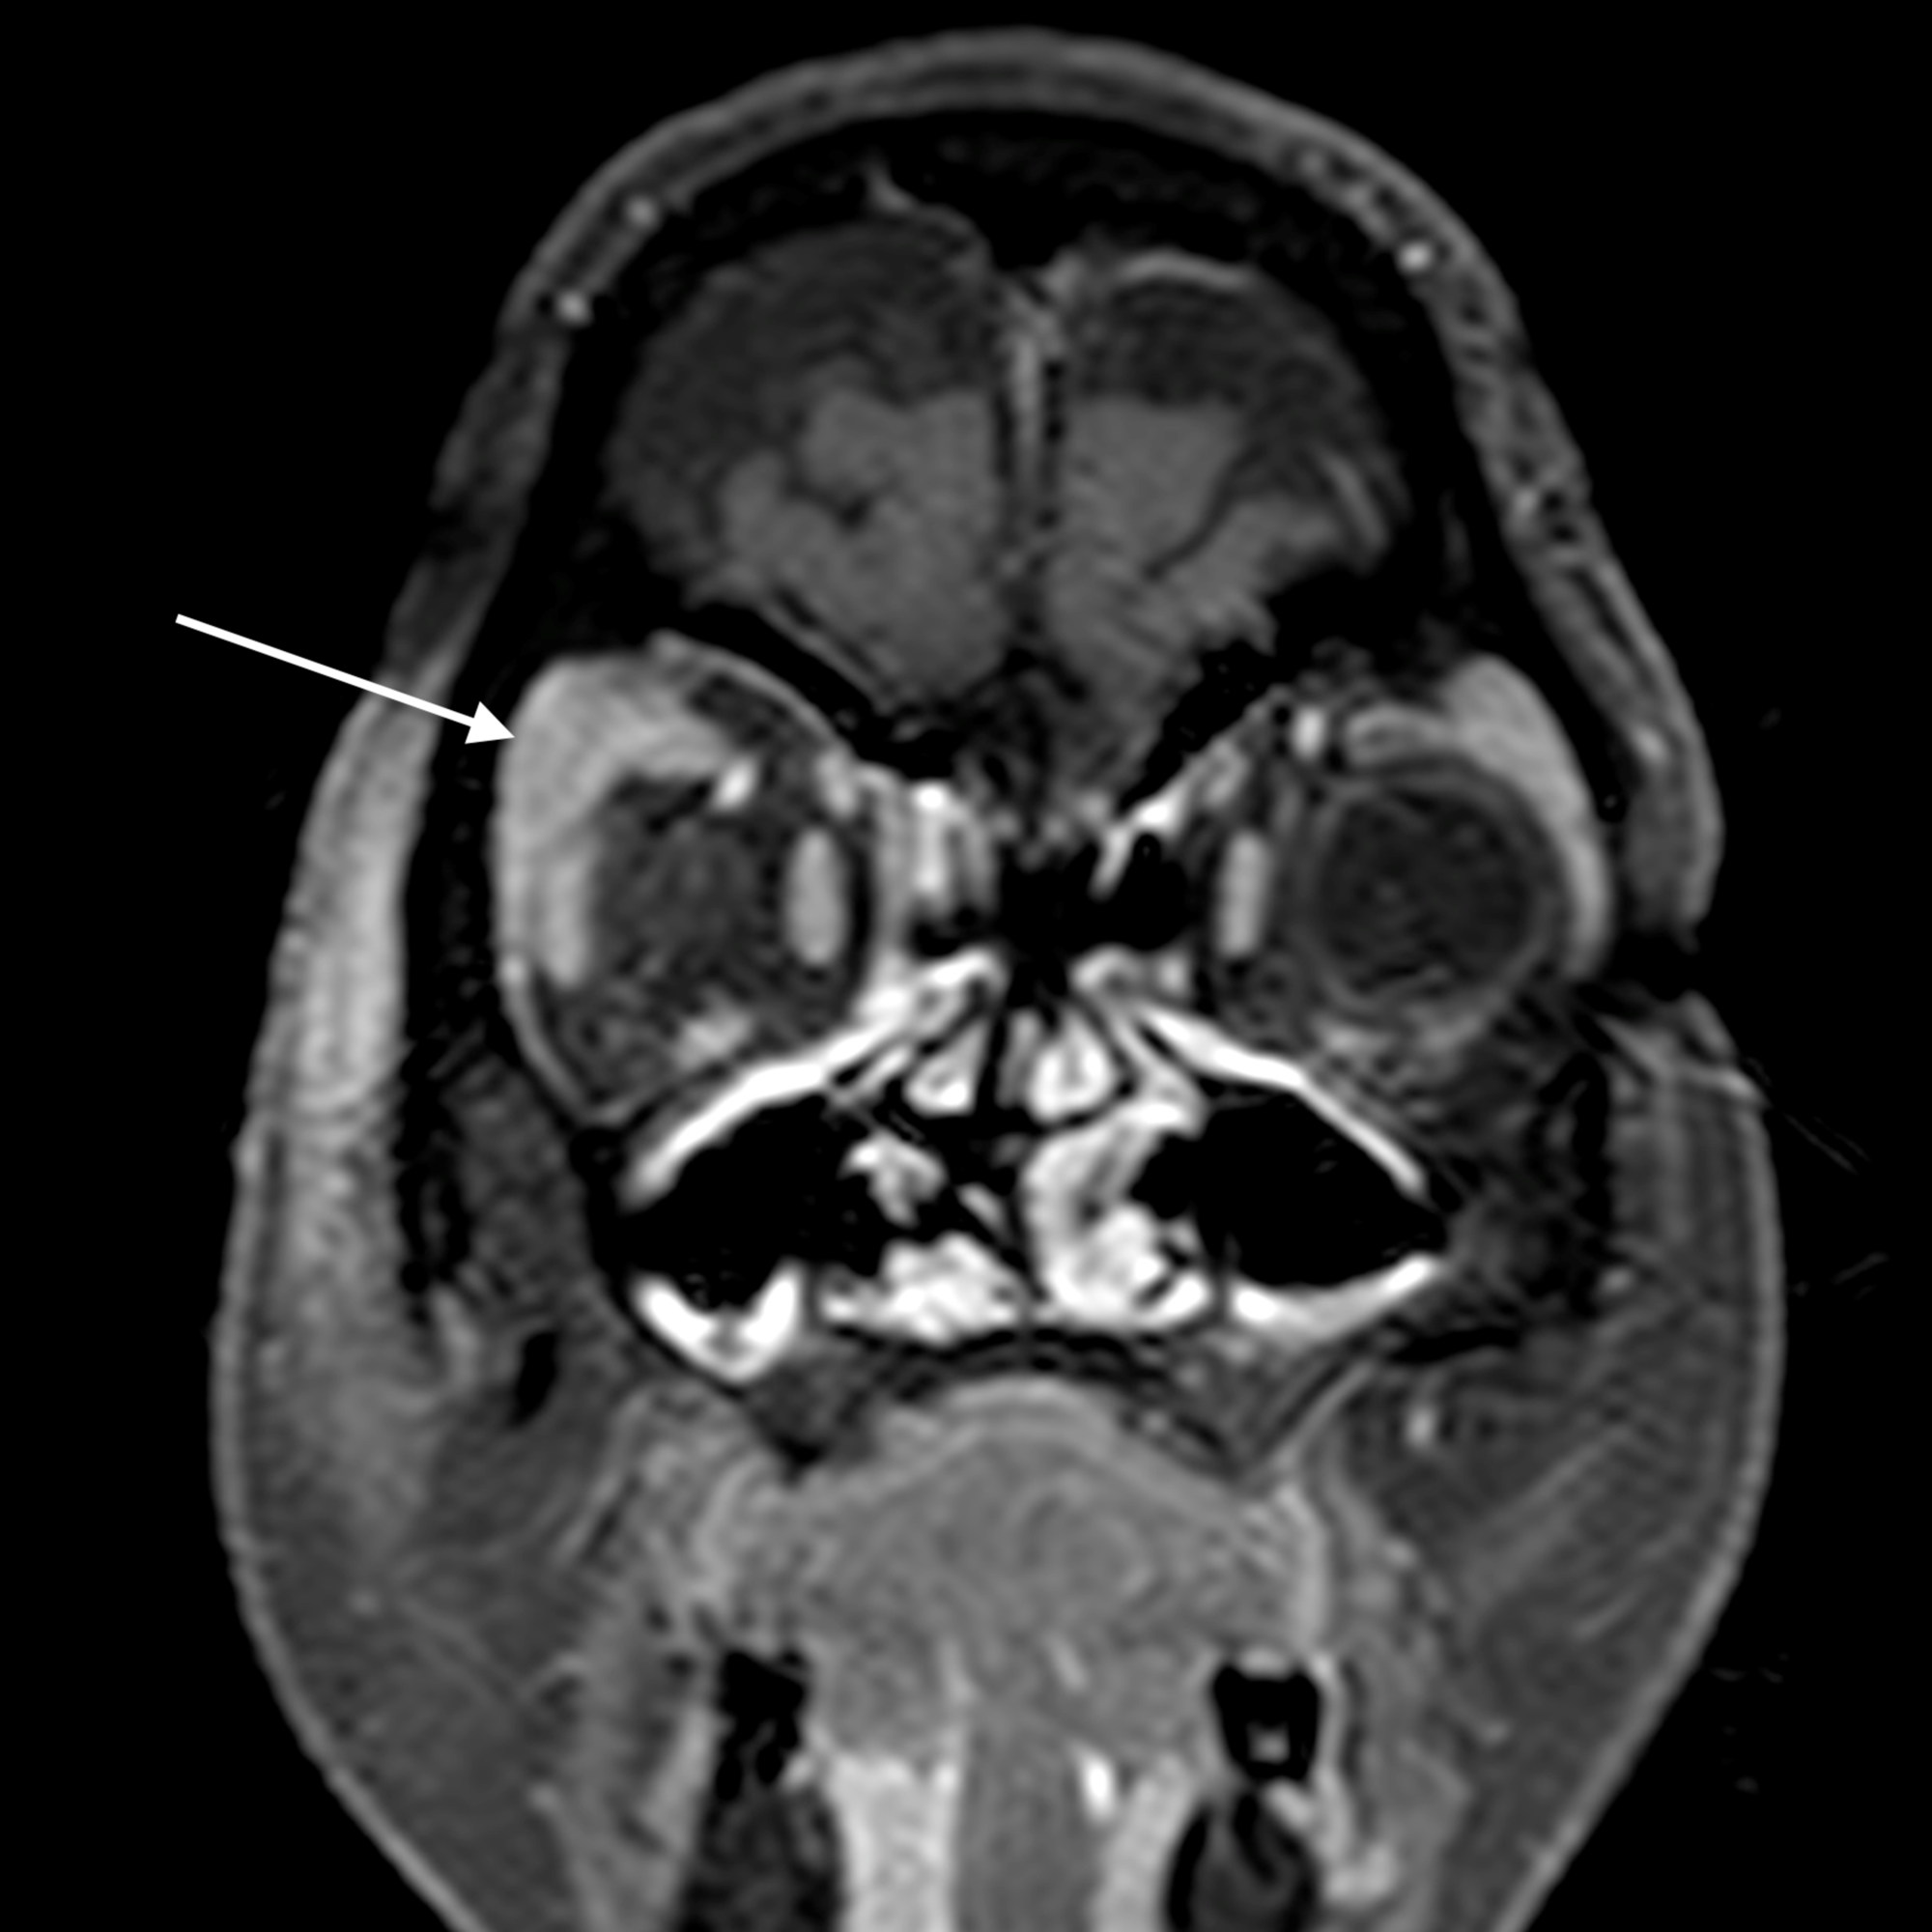

The main complications of orbital cellulitis (Figures 2-4) encountered in our study were:

1. An orbital abscess (Figures 5-6);

2. Preseptal cellulitis and abscess (Figures 7-8);

3. Periorbital cellulitis (Figures 9-10);

4. Dacryoadenitis (Figures 11-12);

5. Optic neuritis/perineuritis (Figure 13);

6. Cavernous sinus thrombophlebitis and thrombosis (Figure 14).

The most common complication of orbital cellulitis was orbital/periorbital abscess formation (eight cases, 53.3%), followed by optic neuritis (four cases, 26.67%), intracranial involvement (four cases, 26.67%), dacryoadenitis (three cases, 20%) and cavernous sinus thrombophlebitis (three cases, 20%).

Orbital cellulitis causes diffuse, oedematous infiltration of the orbital connective tissue that is best demonstrated by the high signal intensity in T2-weighted fat-saturated sequences. Other findings are swelling and ill-defined margins of the extraocular muscles and exophthalmos [2]. Orbital cellulitis may be complicated by an abscess, which may form in the extraconal or intraconal orbit separate from the bone [3].

Contrast administration is imperative to distinguish an abscess from a phlegmon and edema. The center of the abscess shows restriction of diffusion on diffusion-weighted imaging (DWI) and demonstration of this finding may obviate the need for intravenous contrast administration in patients who have a contraindication to contrast especially the diabetics who commonly have associated nephropathy. MRI has a high sensitivity in the detection of cavernous sinus thrombosis, which is an uncommon but serious complication of orbital cellulitis and paranasal sinusitis. T2W fat-suppressed sequence is especially useful for the detection of edema related to orbital infections. Poor bony detail, susceptibility to artifacts, lack of wider availability, and higher costs remain disadvantages of MRI.